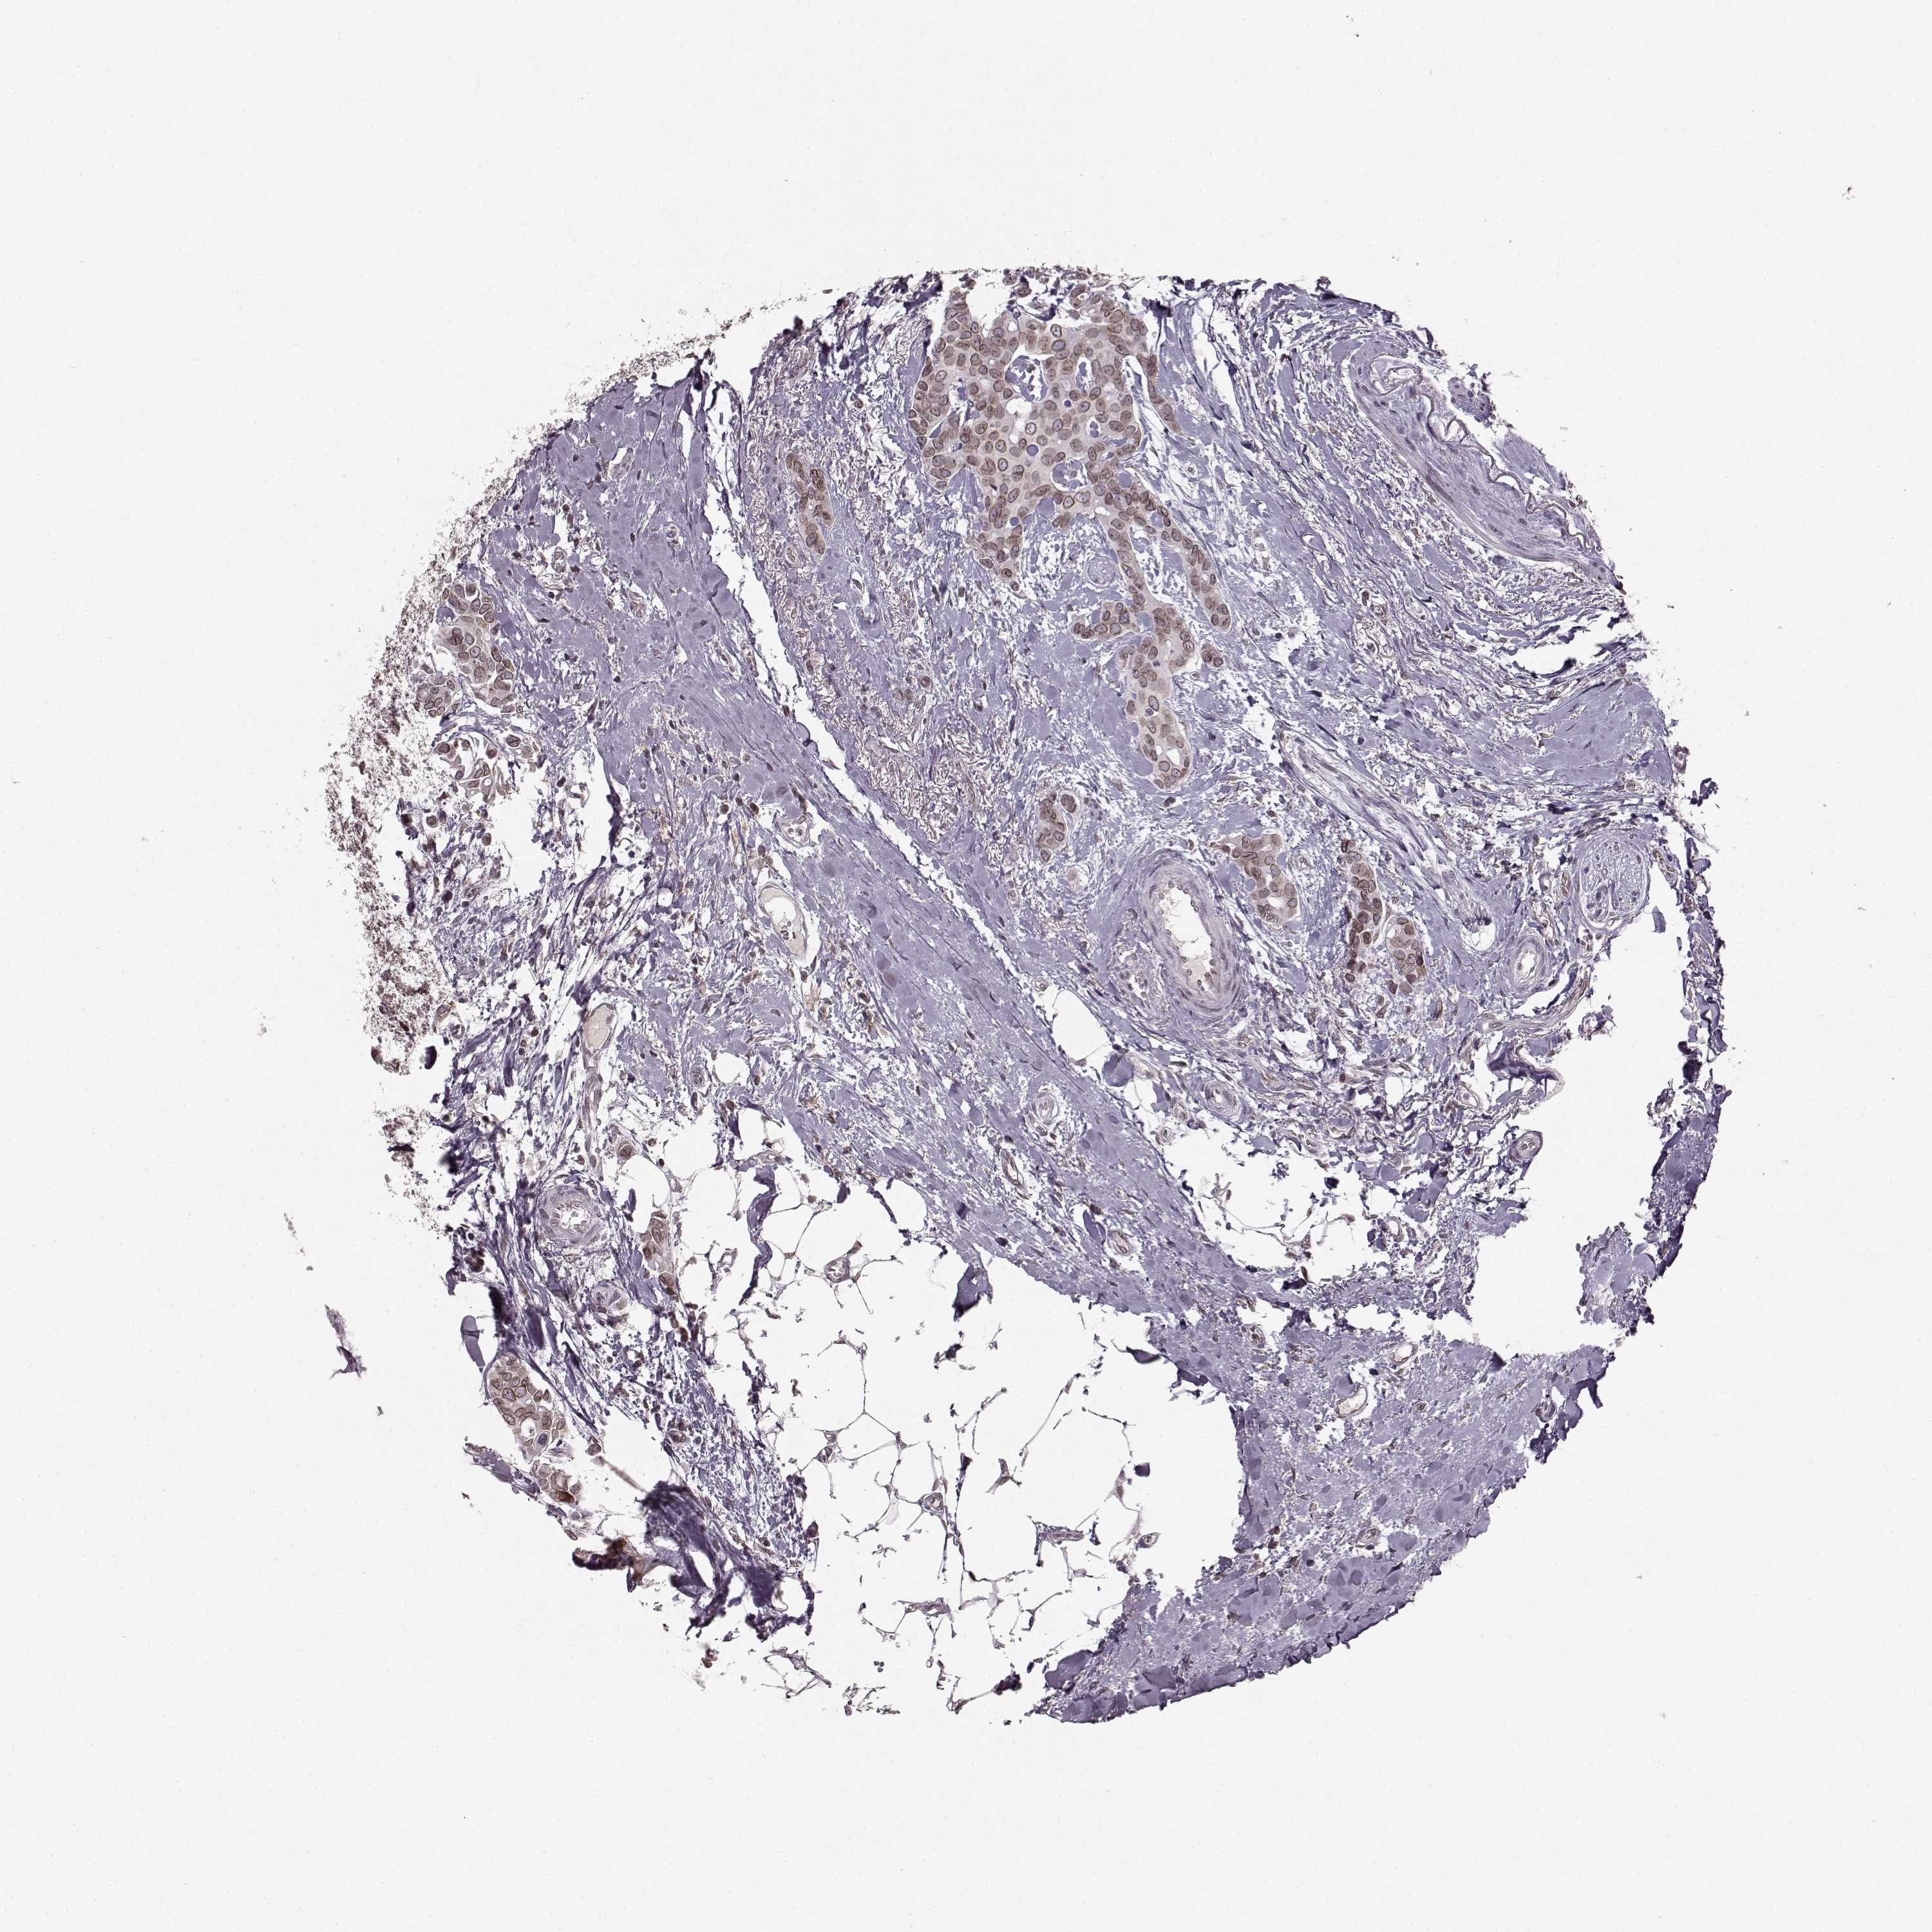

BRCA TCGA BRCA VALIDATION PROTEIN EXPRESSION